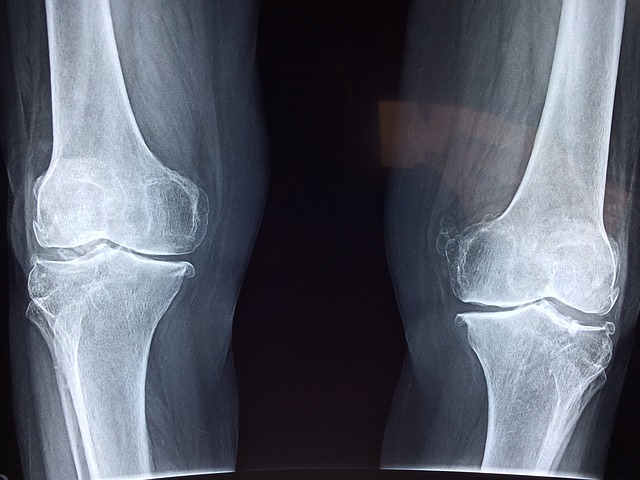

먼저, 면역 시스템의 과도한 반응이 크론병과 관절염의 공통된 특징입니다. 크론병은 면역 시스템이 장 내부의 정상적인 세포와 미생물을 공격하여 염증을 일으킴으로써 발생합니다. 이에 따라 장의 벽이 손상되고 염증이 지속되면서 크론병의 증상이 나타납니다. 관절염은 면역 시스템이 관절을 비정상적으로 인식하여 염증을 유발하는 질환으로, 면역 시스템의 과도한 반응이 관절 염증을 일으키는 원인이 됩니다.

두 질환에서 발생하는 염증 과정도 공통된 특징입니다. 크론병과 관절염은 염증이 주요한 병리 생리학적 특징이며, 면역 세포와 염증 매개물질의 상호작용을 포함한 복잡한 염증 과정이 진행됩니다. 염증은 면역 세포의 활성화와 염증 매개물질의 분비로 인해 발생하며, 조직 손상과 염증 반응의 연쇄적인 확산을 초래합니다. 크론병과 관절염에서는 이러한 염증 과정이 장 내부와 관절에서 진행되어 증상을 야기합니다.

크론병과 관절염은 장과 관절 사이의 연결 또는 상호작용을 나타내는 장-관절 축 연결을 가지고 있습니다. 이 연결은 두 질환 간의 관련성을 보여주며, 크론병과 관절염이 동시에 발생하거나 한 질환이 다른 질환을 유발하는 경우가 많이 있습니다.

장-관절 축 연결은 면역 시스템과 염증 과정에서 중요한 역할을 합니다. 크론병은 장 내부의 염증과 관련된 만성 장질환으로 알려져 있습니다. 장 내부의 염증은 면역 시스템의 비정상적인 반응에 의해 시작되며, 이는 관절염의 발병과 진행에도 영향을 줄 수 있습니다. 따라서 크론병에서 발생하는 염증은 관절로 확산되어 관절염을 유발할 수 있습니다.

또한, 장-관절 축 연결은 염증 매개자나 화학 물질의 상호작용을 통해 크론병과 관절염 간의 연결을 형성할 수 있습니다. 장 내부의 염증 매개자가 혈류를 통해 관절로 이동하면 관절 내부에서도 염증이 발생할 수 있습니다. 이러한 염증 반응은 관절의 통증, 부종, 운동 제한 등을 초래할 수 있으며, 장-관절 축 연결을 통해 크론병과 관절염 간의 증상이 상호 영향을 줄 수 있습니다.